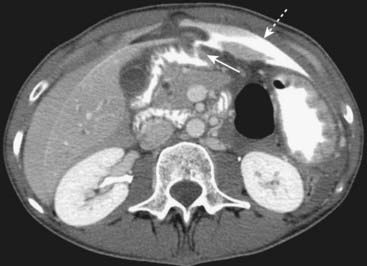

Figure 18-11 Free air from bowel perforation.

With the patient lying supine for this CT scan, free intraperitoneal air (solid white arrows) rises to the highest part of the abdomen beneath the anterior abdominal wall. Most cases of free intraperitoneal air (pneumoperitoneum) are due to perforations from gastric and duodenal ulcers.

image Extraluminal contrast or extraluminal air. Indicates the presence of a bowel perforation (Fig. 18-11).